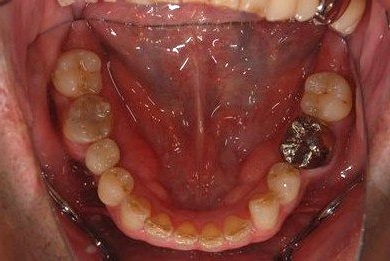

| 性別/年齢 | 男性 / 37歳 | ||||||||||||||||||||||||||||||||

| 主訴 | 前歯(2本)の欠けの治療 | ||||||||||||||||||||||||||||||||

| 治療方針 | 右下欠損部分をインプラント治療にて、機能的・審美的回復を行う。 | ||||||||||||||||||||||||||||||||

| 治療内容 | インプラント1本、メタルボンドセラミッククラウン1本 | ||||||||||||||||||||||||||||||||